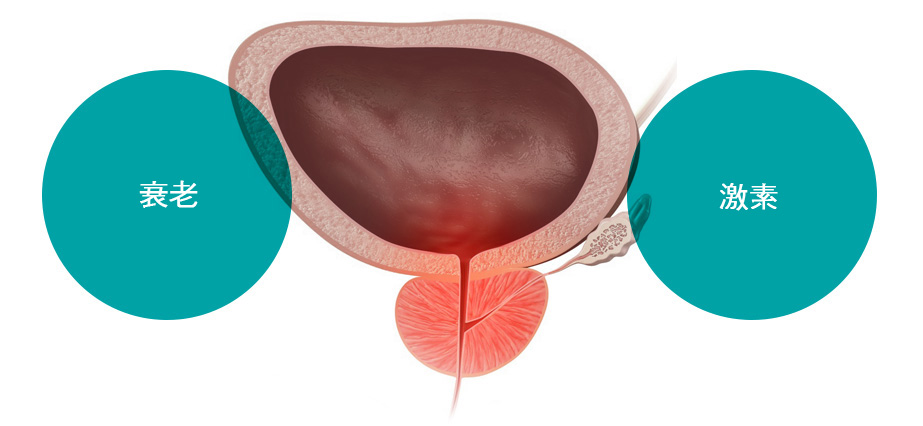

前列腺是男性独有的生殖器官,位于膀胱下方和直肠前方。它覆盖尿道,即尿液通道,并产生约 30% 的精液。如果前列腺肿大,就会压迫尿道,导致多种泌尿系统疾病。

前列腺是男性独有的生殖器官,位于膀胱下方和直肠前方。它覆盖尿道,即尿液通道,并产生约 30% 的精液。如果前列腺肿大,就会压迫尿道,导致多种泌尿系统疾病。